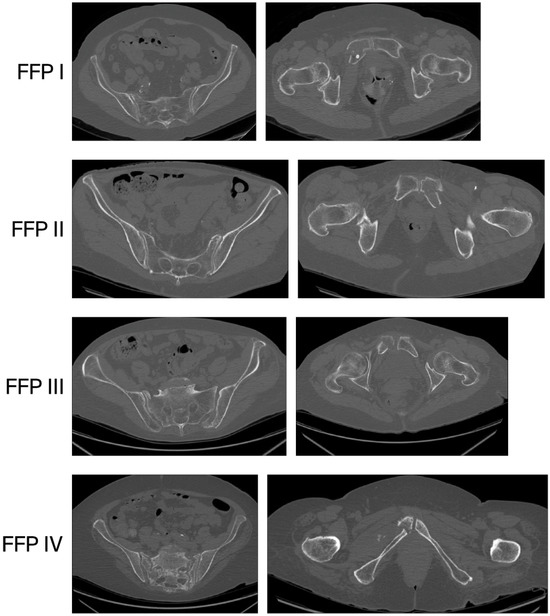

The Impact of CT Imaging on the Diagnosis of Fragility Fractures of the Pelvis: An Observational Prospective Multicenter Study

Background/Objectives: Fragility fractures of the pelvis (FFPs) are a significant concern in the elderly population, often leading to severe morbidity and mortality. This study aims to evaluate the diagnostic challenges, clinical outcomes, and mortality rates associated with FFPs in patients referred to multiple hospitals. Methods: A total of 99 patients with suspected pelvic fragility fractures were enrolled between January 2023 and June 2025. Initial diagnoses were made using plain X-rays, with computed tomography (CT) utilized to assess posterior ring fractures. Data on demographics, fracture types according to the Fragility Fracture of the Pelvis (FFP) Classification, hemoglobin levels, and mortality rates were collected and analyzed. Results: The findings revealed that while plain X-rays identified only anterior pelvic ring fractures, CT scans detected posterior ring fractures in 60.6% of cases. Patients with Nakatani II and III pelvic ramus fractures exhibited the most significant decreases in hemoglobin levels. The overall mortality rate was found to be 13.13%, with the highest rates observed in FFP I (13.5%) and FFP II (11.9%) groups. Conclusions: The findings of this study underscore the importance of CT imaging in the diagnosis of FFPs and highlight the need for close monitoring of hemoglobin levels in affected patients. This study also emphasizes the increased mortality risk associated with more complex fracture types. Future research should focus on evaluating functional independence and treatment outcomes to guide clinical decision-making in managing fragility fractures of the pelvis. Full article

Show Figures

Figure 1